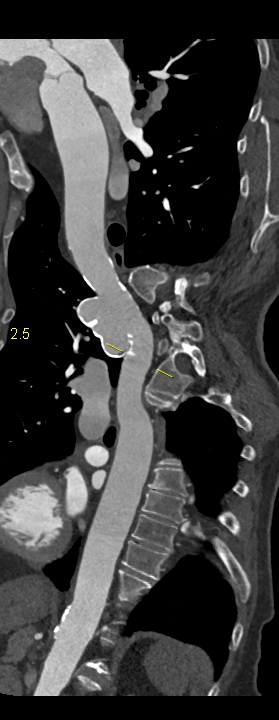

Figura 1: reconstrucţie aortică în planul vasului

Pacient cu traumatism prin accident de mașina în antecedente; efectuează examinare CT de artere coronare si aorta toracică. Se evidențiază un pseudoanevrism de istm aortic cu prezenta de calcificări arciforme pe contur.

Pseudoanevrismul de istm aortic este practic o ruptură conținută de aortă şi apare la pacienții care suferă un traumatism cu decelerare importantă. Deseori apare ca descoperire întâmplătoare tardivă, mai ales daca traumatismele au avut loc cu mulți ani in urma când examinarea CT nu se efectua de rutină la acest tip de pacienți.